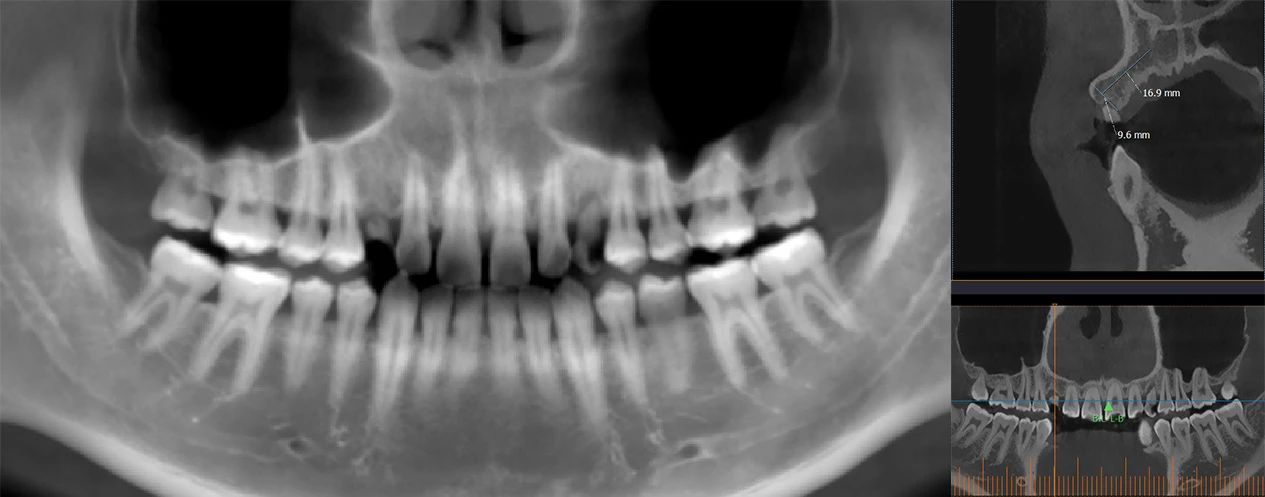

CBCT Assessment:

Tooth 13 area: Bone height ~16mm, width ~9mm

Available interdental space ~6mm